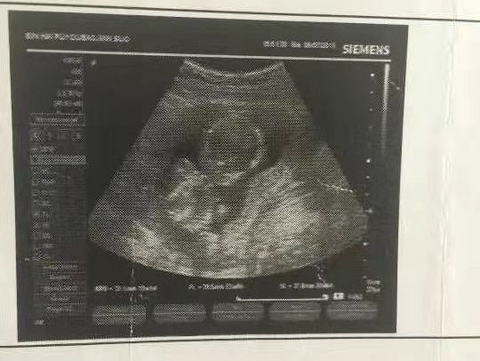

四维通过,往返车程6个小时屁股坐痛但也抵不过内心的激动

以前在重庆工作公司入职做健康体检,然而知道了国宾医院从那次也就添加了客服小姐姐的微信,体检结果没去医院取是她电子扫描发给我的,第一次的体验感很好不论环境还是服务,虽然离家较远也宁愿来国宾做四维。 堵车高速开了3个多小时终于到啦